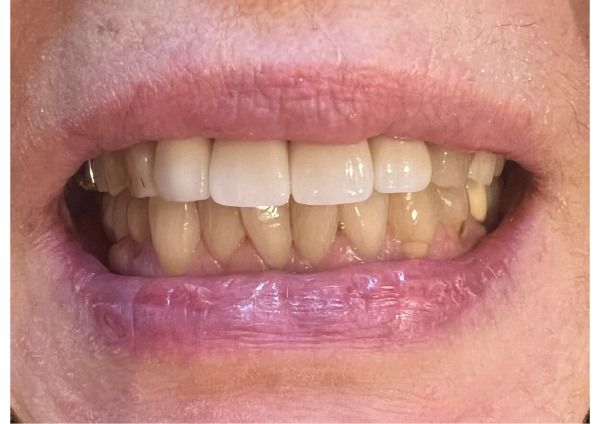

患者様は最初、金属のバネが見えないノンクラスプデンチャーを希望されていました。しかし、左上は3本分の入れ歯となるため片側だけのコンパクトな設計が難しい状況でした。

そこで、長く使えて修理可能な金属床をご提案したところ、「できる範囲で金属は見えないようにしてほしい」とのご希望をいただきました。入れ歯は左側の前から3番目にかかるため、見える部分はプラスチック、裏側をチタンで支える設計としました。

以前の入れ歯より大きいため違和感はあるものの、チタン素材のため軽く、取り外しも問題なくできているとのことでした。

患者様は趣味で歌を歌われることから、見た目をとても気にされていましたが、金属が見えるのは右側のわずかな部分のみで、仕上がりに非常に満足しているとおっしゃっていました。